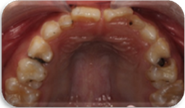

诊断:64,65,84,85慢性根尖周炎;54DOL深龋,55O中龋;74OD,75MO继发深龋 处置:64,65,84,85根管治疗 54DOL,55O行充填治疗 74OD,75MO去除旧充填体后充填治疗

乳牙根管治疗术是治疗乳牙根尖周病的有效方法,通过根管预备和药物毒去除感染物质对根尖周组织的不良刺激,并用可吸收的充填材料充填根管,促进根尖周病愈合。 在第一恒磨牙未完全萌出之前,为防止乳牙早失造成第一恒磨牙近中移位,对于第二乳磨牙的较大面积根尖周病变我们采取保守治疗,根管治疗后需定期复查,一旦发生病变扩大及时拔除,在此病例中第一恒磨牙未完全萌出,我们对65,85进行试保留,半年后临床检查无异常,x线片显示病变较初诊时缩小,建议继续观察。